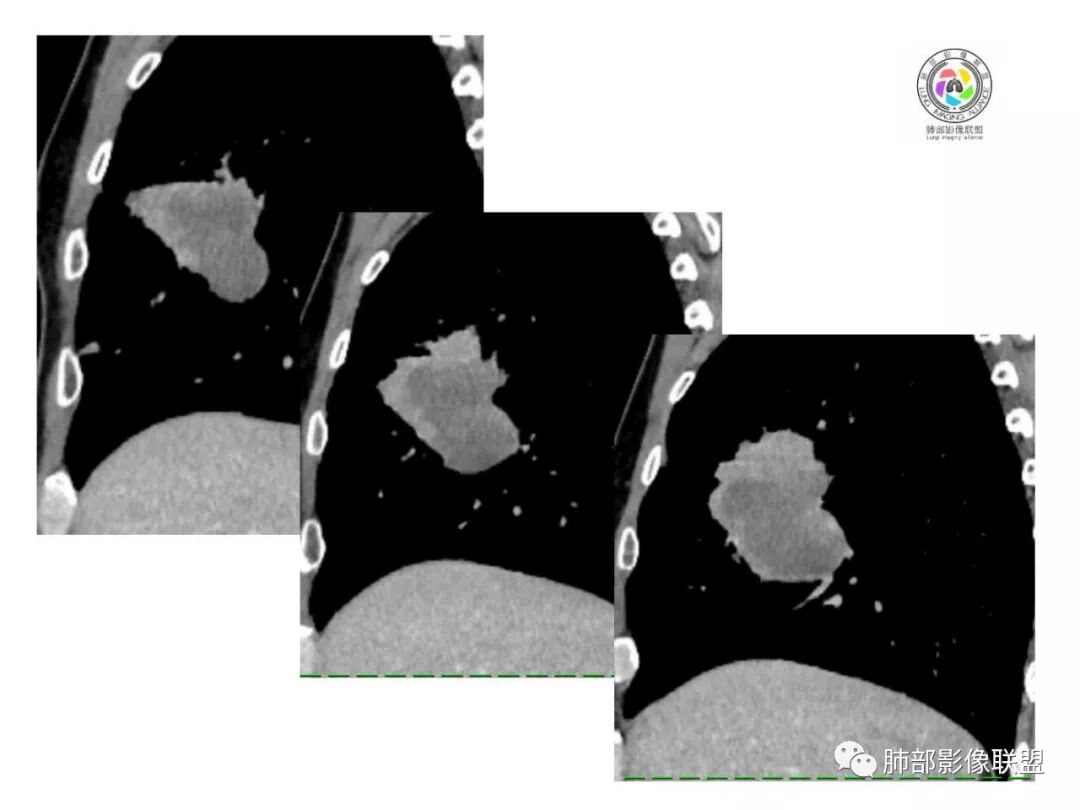

1.具有肉瘤的特性:肿瘤体积一般较大,直径约大于5cm,边缘清楚、光整,由于肿瘤生长迅速,可见大片坏死,坏死边界清楚;常见支气管推移。

2.具有癌些特性:如分叶、短毛刺、空洞,但是钙化及胸膜凹陷征少见,病灶往往是直接侵犯胸膜,可以远处转移,肺门及纵隔淋巴结可明显肿大;

3.强化方式:增强后病灶以环状强化为主,病灶周边多以癌组织为主,血供丰富,病灶中心区则以肉瘤成分为主,血供较差,易出现粘液样变性、坏死、出血,坏死边界清楚,所以增强CT对PSC与普通型肺癌有一定的鉴别价值。

1.本病例结合病理结果及影像综合分析,应该符合肉瘤样癌,上皮成分是腺癌为主;肿块的边缘毛刺、分叶及周围癌型淋巴管炎征象有符合腺癌的影像表现之处。

2.肿块巨大局部边缘膨隆、光整,坏死较彻底;明显跨叶生长(途经发育不全叶间裂或肺门,注意患者没有胸水),支气管阻塞伴推移等,这些更符合肉瘤的特性。

3.坏死区边界较清楚(皮囊样),环形强化明显,病灶内血管穿行等,都不符合我们常见的鳞癌。